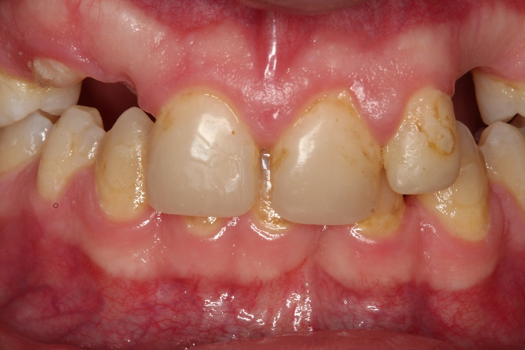

Fig 6. Photograph, 18-year-old brother.

Figure 6

Figure 5 through Figure 12 exemplify what currently may present in private dental practices with these types of patients. Four brothers aged 14 years to 27 years all suffered from obstructed airways; high incidence of caries of dentin, enamel, and cementum; moderate periodontal disease; collapsed vertical; undiagnosed OSA; and the potential for increase in comorbidities such as diabetes, cardiovascular disease, dementia, cancer, high blood pressure, and others. Symptomology was presented throughout the young lives of the brothers in this family. The parents were unaware that the dental agenesis and premature permanent tooth extraction could have led their sons into severe health issues as they matured.

Swift intervention took place with caries control, periodontal care, orthodontic evaluation for arch form development to aid in the development of facial bones and creating an improved upper airway with nasal patency. These interventions were followed up with definitive implant therapies and rapidly advancing restorative technology and materials. Thus, not only were these young men's smiles restored, they also were provided with the opportunity to regain their dignity when they become confident with their new smiles.